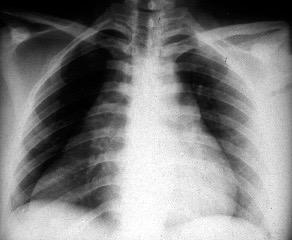

Carcinoma microcítico con síndrome de VCS